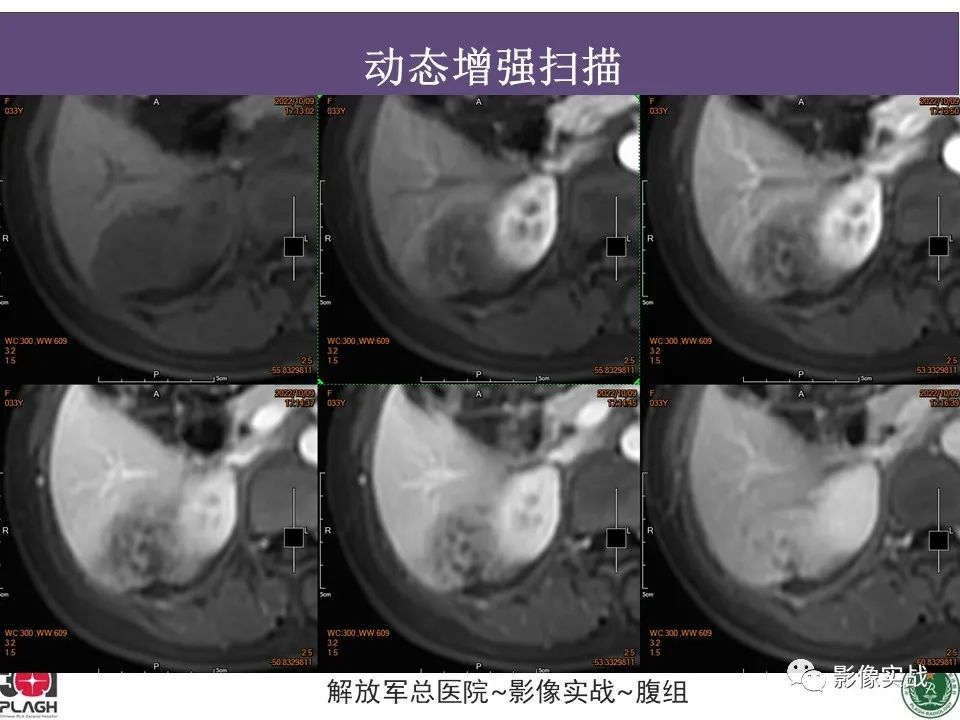

【病例】肝内胆管细胞癌1例MR影像-5

【病例】肝内胆管细胞癌1例MR影像-6